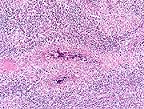

Group of H. deletrix larva within the granulomatous inflammation in a horse kidney. (HE, 200X, 83K)

Higher magnification of the field above. (If you look closely, you may be able to imagine a rhabditiform esophagus). (HE, 400X, 51K)

Morphologic Description: There are multifocal to coalescing foci replacing the renal parenchyma. The foci contain cross and longitudinal sections of a nematode with a smooth cuticle, pseudocoelom, a tubular digestive tract lined by low cuboidal epithelium, tapered tail, and rhabditiform esophagus with a corpus:isthmus:bulb ratio of 3:2:1. Mature females, larvae, and eggs are present, and females rarely contain ova in various stages of development. The parasite is surrounded by a mixture of fibrin, neutrophils, cellular debris, epithelioid macrophages and multinucleated giant cells that are contiguous with coalescing infiltrates of plasma cells, lymphocytes, and eosinophils in a loose fibrovascular stroma. Occasional tubules are present among the inflammatory cells, and these are often lined by necrotic or regenerating epithelial cells and contain proteinic and cellular debris.

H. deletrix is distinguished by a uterus that is dorsoflexed at the ovary and ventroflexed at the vulva, a tapered tail, and a rhabditid esophagus with a corpus:isthmus:bulb ratio of 3:2:1. All eight species are considered free-living nematodes found in soil and decaying organic material. However, the free-living stages of H. deletrix have not been identified, and only adult females, larvae, and eggs have been reported from tissues of horses and human beings. The brain is the most commonly involved tissue in horses, followed by the kidneys, oral and nasal cavities, lymph nodes, lungs, liver, ganglia, bone and eye. The parasite may induce an acute syndrome of cerebral vasculitis and hemorrhagic necrosis, as well as granulomatous lesions in brain and other tissues. Renal infections produce cream-colored masses which may resemble neoplasms grossly. The method of infection is unknown. It is presumed that infection occurs by contamination of mucosal, cutaneous, or ocular wounds by larvae in the environment, with hematogenous dissemination accounting for the high incidence of kidney and brain involvement. In addition, pulmonary infection in two foals has lead to the suspicion that infection may occur by inhalation, transplacental, or transmammary routes.